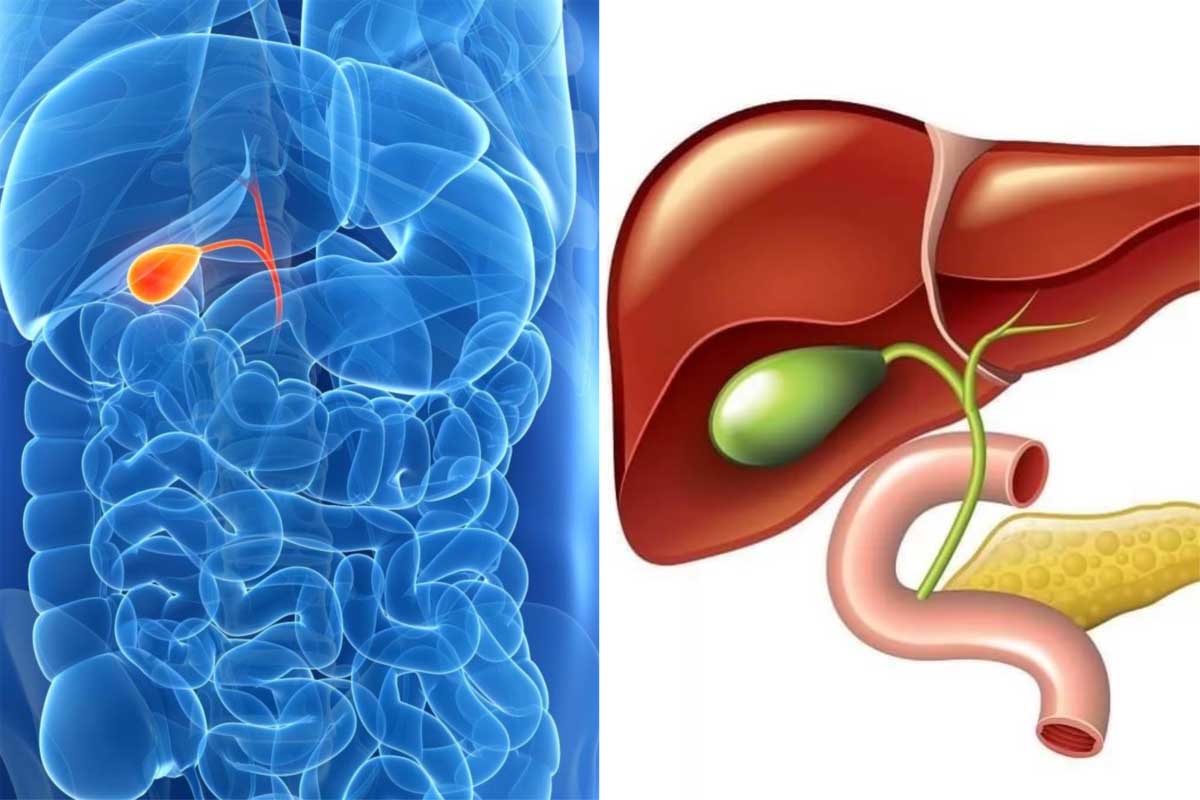

Анатомия и особенности Гартманова кармана желчного пузыря